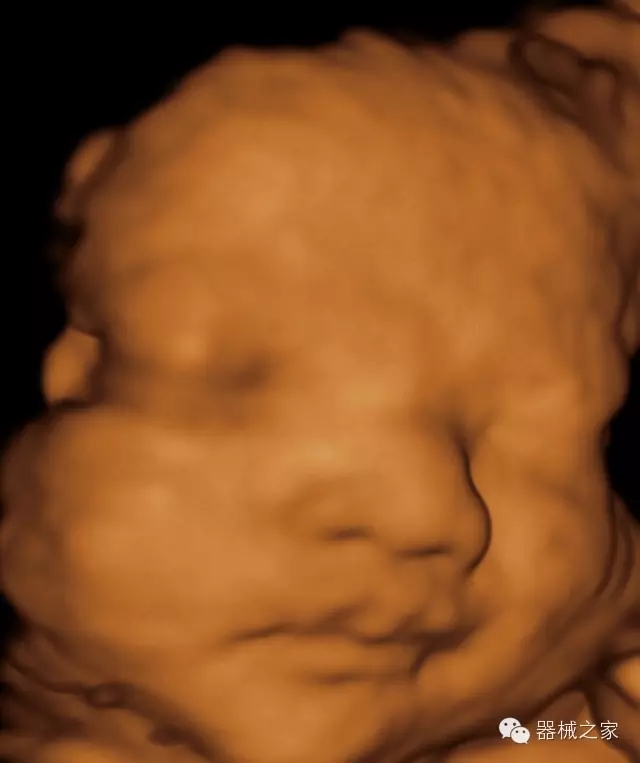

臨床圖片賞析

·高效3D/4D成像技術(shù):高速的4D幀頻,豐富的3D成像模式,智能斷層切片功能;